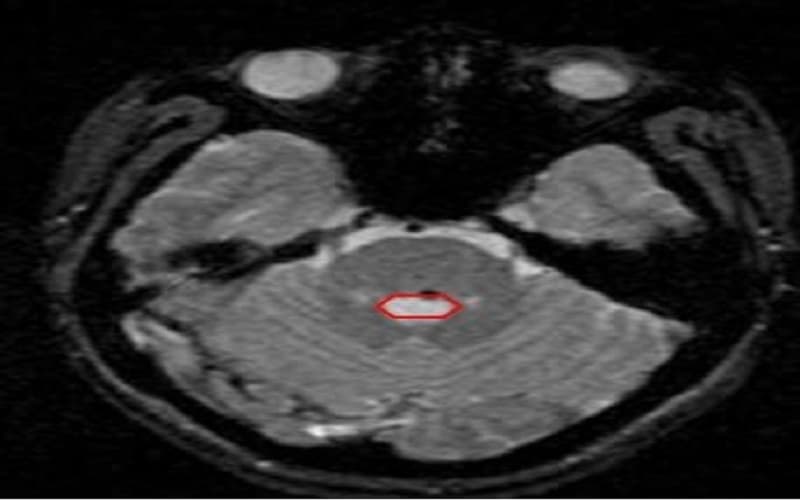

U mạch máu dạng hang (dị dạng thể hang) là một tập hợp bất thường của các mao mạch (những mạch máu rất nhỏ) kết tụ sát nhau thành từng cụm. Bên trong khối tổn thương có các khoang chứa máu, được ngăn cách bởi mô liên kết. Do thành mạch mỏng và cấu trúc nâng đỡ kém hơn bình thường, các mạch này dễ rò rỉ hoặc chảy máu.

U mạch máu dạng hang có thể xuất hiện ở nhiều vị trí trong cơ thể, nhưng thường gặp nhất ở não, thân não và tủy sống. Ngoài ra, có thể xuất hiện u lành mạch máu dạng hang ở lưỡi, da, gan hoặc mắt, tuy nhiên các vấn đề nghiêm trọng chủ yếu xảy ra khi tổn thương nằm tại não hoặc tủy sống.